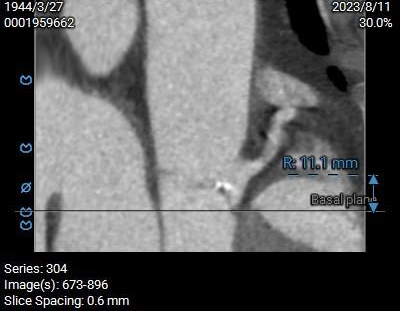

双侧冠脉开口高度可,左侧瓣叶略长,预估左侧冠脉遮挡风险较低:

双侧冠脉高度开口可,窦部较为扁平,左冠瓣叶较长,预估左冠存在一定遮挡风险,球扩及工作位密切关注冠脉血流灌注,必要时冠脉保护。